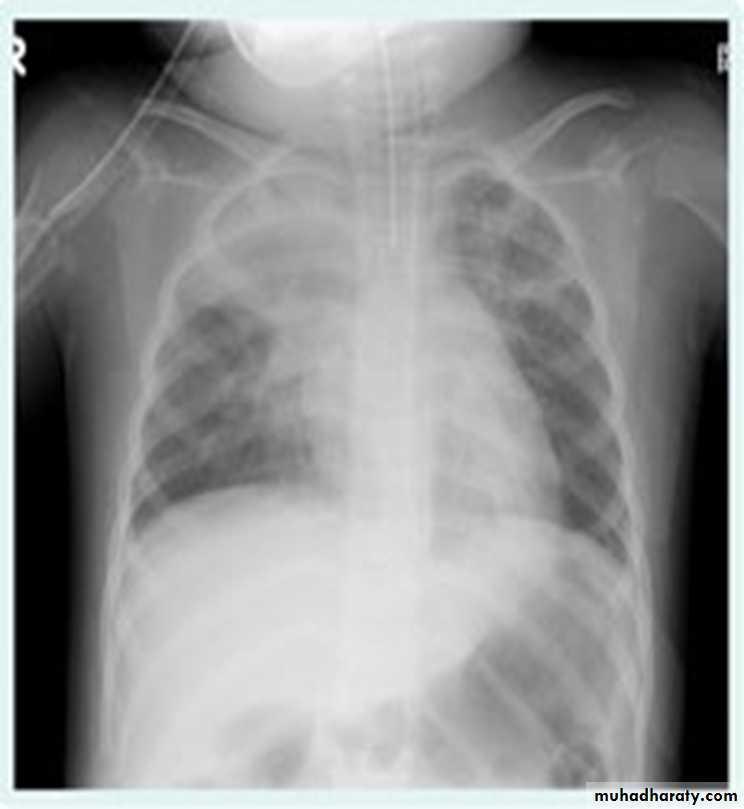

Lobular consolidation ( broncho pneumonia )

Very important to consider that pulmonary edema in normal sized heart have close similar appearance to broncho pneumonia

The important Golden Key differentiation is the cardiac size being enlarged in pulmonary edema .

36.lobuler consolidation (lobular pneumonia )37.discussion